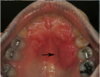

What is this radiographic & clinical findings?

Periapical cyst

shows inflammation at site

abscess developed fistula tract thru

soft tissue. Pt will have pain until

pressure is released